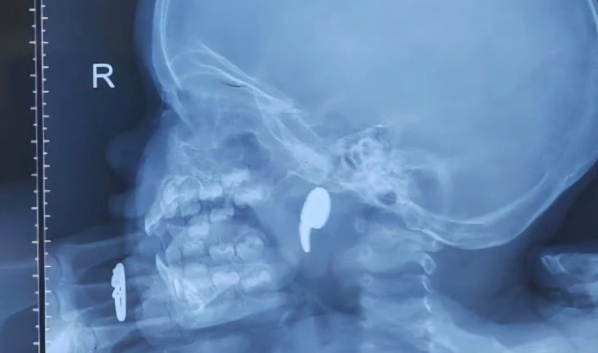

Рентген подтвердил наличие инородного тела. Девочку госпитализировали в ЛОР-отделение.

Выяснилось, что малышка играла магнитом в форме запятой. В какой-то момент она начала задыхаться, и мама попыталась извлечь предмет пальцем. После этого магнит сместился глубже — в носоглотку.